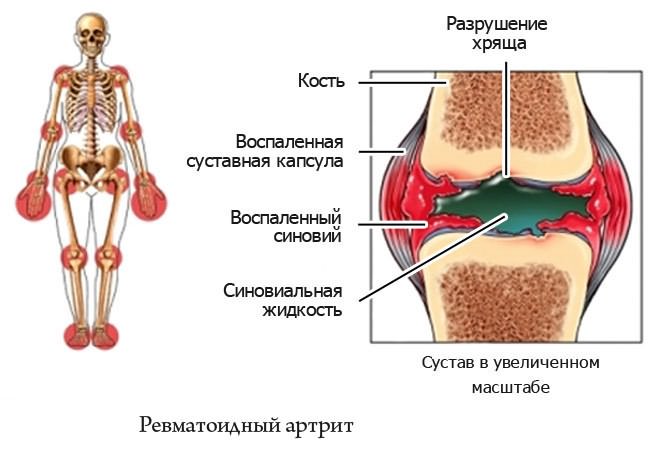

Коленные суставы и ревматоидный артрит: фото и информация